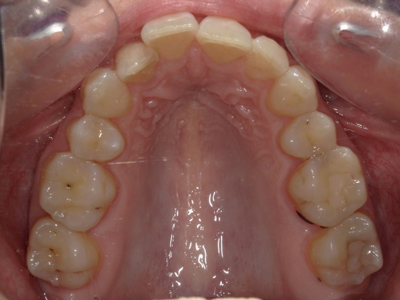

Arcade maxillaire avant traitement orthodontique, séquelles de maladie parodontale